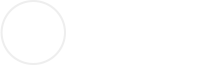

爆裂性骨折是眶部挫伤所致的眶壁骨折,眶缘完整,软组织嵌顿以及典型临床症状的一种单纯的眼眶外伤病症。

眼眶爆裂性骨折多为车祸、体育运动、工业事故、及斗殴等,致伤物较眼眶大,自前方直接打击眼睑和眼球所致。发生机制有眶内流体压力学说和眶底扣压力学说。

1.眶内流体压力学说认为,外力作用于眶前部软组织,致眶内压力突然增高,一部分被眶内软组织吸收,按液压传递原则,眶内压力导致眶壁最薄弱的部位发生骨折。眶壁筛骨纸板员薄,眶下沟后部也较薄,仅0.5mm,是容易发生骨折的部位。由于流体压力同时作用于软组织,而使软组织嵌于骨折处或嵌入上颌窦或筛窦以内。

2.眶底扣压力学说认为,当眶缘受到顿物冲击时,眶底骨质和骨膜向后移位、变形,发生眶底线状骨折和骨膜撕裂,同时将软组织嵌入。当外力作用消失时,眶底骨质很快恢复原位,而软组织复位相对缓慢,导致软组织嵌入骨折处。

1.眶下壁骨折

是爆裂性骨折最多见的部位。16岁以下患者多为下壁。眶下沟较为薄弱,下壁骨折位置多在此处.或在眶下沟的两侧。虽然眶内壁筛骨纸板比下壁更薄,由于年龄小,眶内壁富有弹性,在外力作用时易产生变形,而不至骨折发生。随着年龄增加,内壁骨折机会增加。

2.眶内壁骨折

筛骨纸板也是爆裂性骨折多见部位,可以是单纯眶内壁骨折,骨折也可在眶内下角,包括筛骨纸板及上颌窦内侧部分。成年人眶内壁弹性减弱,其内壁最薄,平均0.2~0.4mm,是其好发爆裂性骨折的解剖因素。